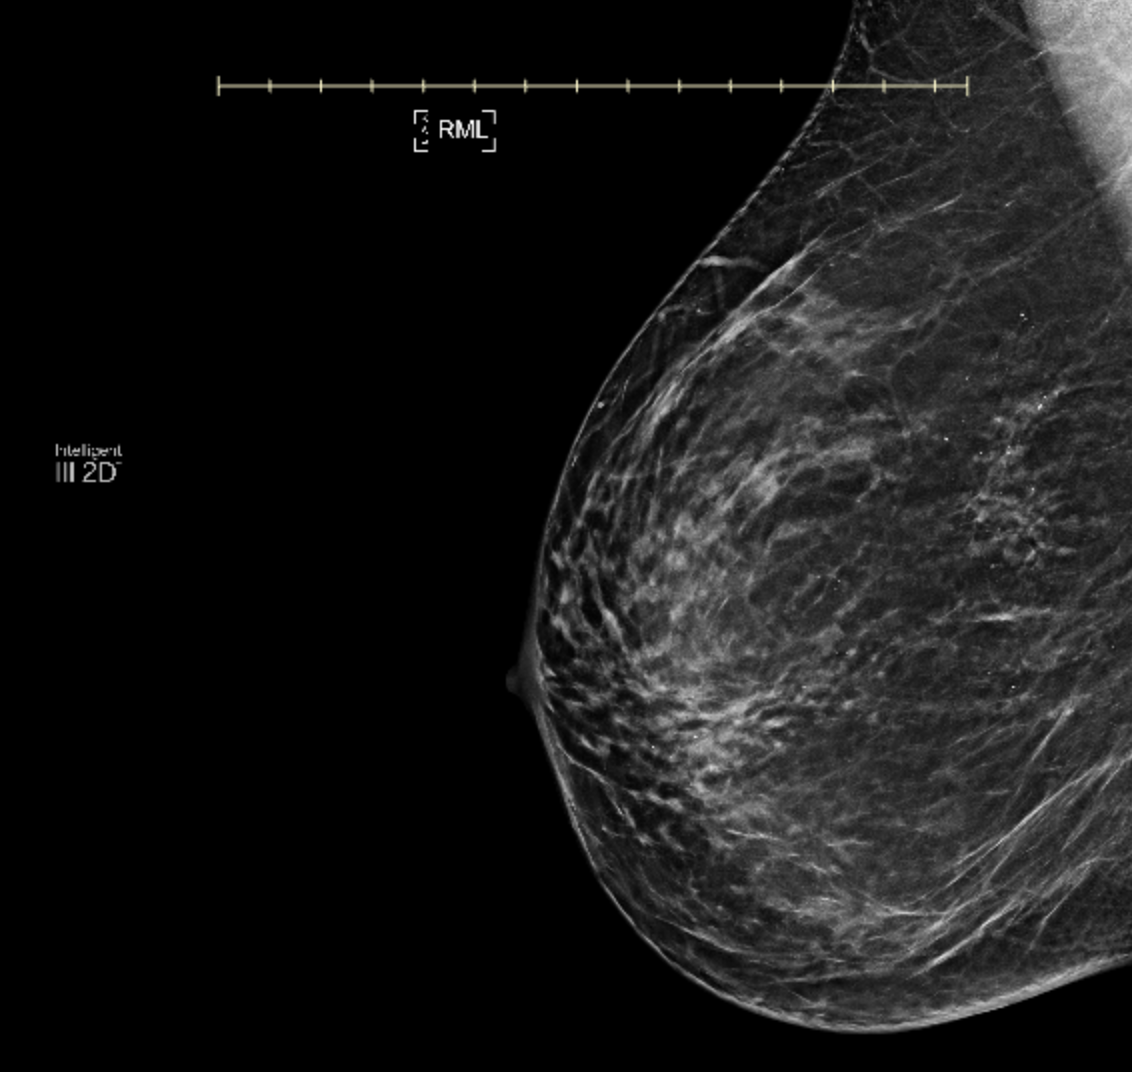

DCIS or Ductal Carcinoma in Situ, Stage 0 breast cancer, or pre-cancer is the most common “breast cancer” diagnosis for women. Found on a routine mammogram as tiny clusters of calcifications (microcalcifications)—small white specks that may suggest abnormal cell growth, it is diagnosed via stereotactic breast biopsy as low, intermediate and high grade as determined by cellular size, shape, growth pattern. A The National Breast Cancer Coalition defines DCIS as NOT CANCER. However, nearly all women diagnosed with DCIS receive treatment, most commonly surgery—either lumpectomy or mastectomy along with radiation and hormonal therapy. In fact, up to one-third undergo mastectomy and the rate for contralateral prophylactic mastectomy (where a healthy breast is also removed) has been steadily increasing.